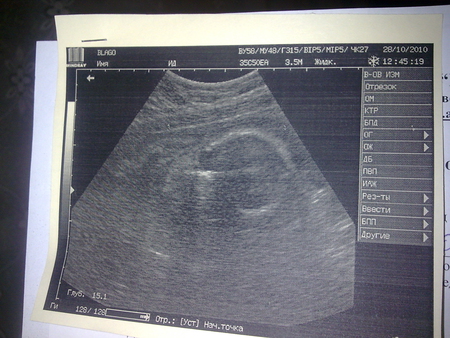

92 24 месяца

Как видно из таблицы, самый маленький размер соответствует росту ребенка 56 сантиметров. Вещей этого размера должно быть немного, так как они быстро становятся малы. В среднем, малыши рождаются длиной 51-53 сантиметра, но сейчас отмечается появление на свет крупных детей ростом 55-57 сантиметров. Поэтому, если УЗИ показывается, что вы носите богатыря, то, возможно, следует покапать первую одежду, начиная с 62 размера.